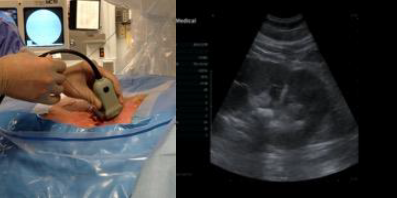

The extension tubing is used to perform an intraoperative retrograde pyelogram. Distension of the calyces provides enhanced visibility during US access. A probe with an attached needle guide is used, and the needle is placed under direct vision into the calyx of interest. US access allows for real-time monitoring of the needle tip.

Confirmation of correct access is aided by fluoroscopic imaging, return of urine and guidewire placement. The guidewire is led all the way down the ureter. The needle is exchanged for a 6-Fr dilator, which is placed all the way past the ureteropelvic junction (UPJ), and the guidewire is exchanged for a super stiff wire. After confirmation the wire is at the level of the bladder, a sub-centimeter skin incision is made. Serial dilators are then used, dilating the fascia up to 14 Fr. A 16 or 18 Fr access sheath with suction capability is used.